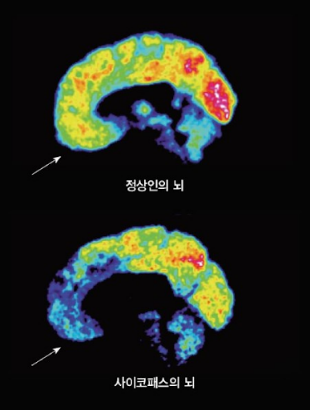

실제 정서적 공감과 인지적 공감은 전혀 다른 심리적 과정으로 각각을 관장하는 뇌 부위도 다릅니다. 인지적 공감은 대뇌피질의 보다 바깥쪽에서 정서적 공감은 보다 안쪽에서 작용합니다. 사이코패스의 제1 특성이 공감 능력 결핍인데, 이때의 공감은 정서적 공감입니다. 아래 그림과 같이 사이코패스의 뇌는 공감 장면에서 뇌 안쪽이 활성화되지 않습니다. 사이코패스는 인지적 공감에는 문제가 없지만, 정서적 공감에 선천적으로 문제가 있는 사람들입니다.

출처: http://psytimes.co.kr/m/view.php?idx=7681

이러한 사이코패스의 뇌 사진은 우리의 착각을 유발합니다. 정서적 공감은 좋은 것, 인지적 공감만은 나쁜 것 같은 생각을 들게 합니다. 하지만, 사이코패스가 정서적 공감 능력 결핍 때문에 흉악범죄를 저지르지는 않습니다. 오히려 제2, 제3 특성인 자제력 부족, 공격성이 범죄와 관련이 높습니다. 정서적 공감이 부족하다고 타인을 공격하지 않습니다. 정서적 공감 부족이 공격성을 설명하는 비율은 단 1%에 불과합니다(Vachon, D. D., Lynam, D. R., & Johnson, J. A. (2014). The (non) relation between empathy and aggression: surprising results from a meta-analysis. Psychological bulletin, 140(3), 751.).